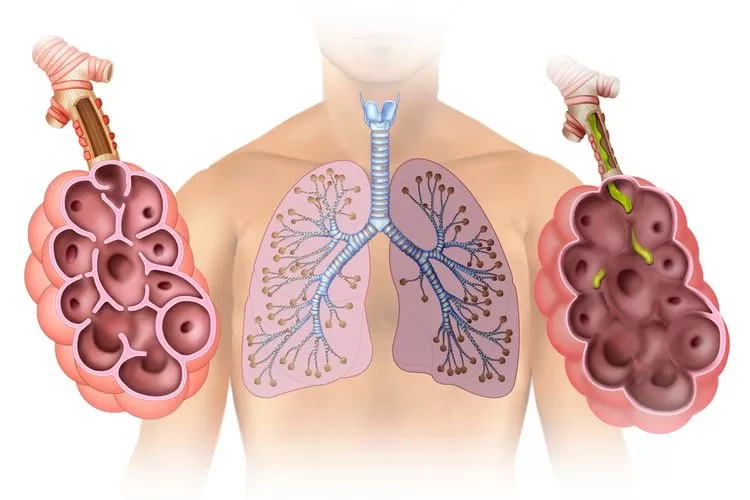

Saluran pernapasan atau tractus repiratorius adalah bagian tubuh manusia yang berfungsi sebagai tempat lintasan dan tempat pertukaran gas yang diperlukan untuk proses pernapasan. Saluran pernapasan pada manusia berpangkal pada hidung atau mulut dan berakhir pada paru-paru. Urutan saluran pernapasan manusia adalah sebagai berikut: Rongga hidung – Faring – Laring – Trakea – Bronkus – Bronkiolus – Alveolus – Paru-paru (pulmo).

Pertukaran udara yang sebenarnya terjadi di alveoli. Dalam paru-paru orang dewasa terdapat sekitar 300 juta alveoli, dengan luas permukaan sekitar 160 meter per segi atau sekitar 1 kali luas lapangan tenis, atau luas 100 kali dari kulit kita.

6. Alveolus

Alveolus merupakan struktur berbentuk bola-bola mungil atau gelembung paru-paru yang diliputi oleh pembuluh-pembuluh darah. Epitel pipih yang melapisi alveoli memudahkan darah di dalam kapiler-kapiler darah mengikat oksigen dari udara dalam rongga alveolus.

Paru-paru terletak di rongga dada tepat di atas sekiat diafragma. Diafragma adalah sekat rongga badan yang membatasi rongga dada dan rongga perut. Paru-paru terdiri dari dua bagian.

Paru-paru kanan memiliki tiga lobus, sehingga lebih besar dari paru-paru kiri yang terdiri dari dua lobus. Paru-paru dibungkus oleh dua lapis selaput paru-paru atau pleura. Di bagian dalam paru-paru terdapat gelembung halus yang merupakan perluasan permukaan paru-paru yang disebut alveolus, dan jumlahnya ± 300 juta buah. Luas permukaan alveolus diperkirakan mencapai 160 m² atau 100 kali lebih luas daripada luas permukaan tubuh.